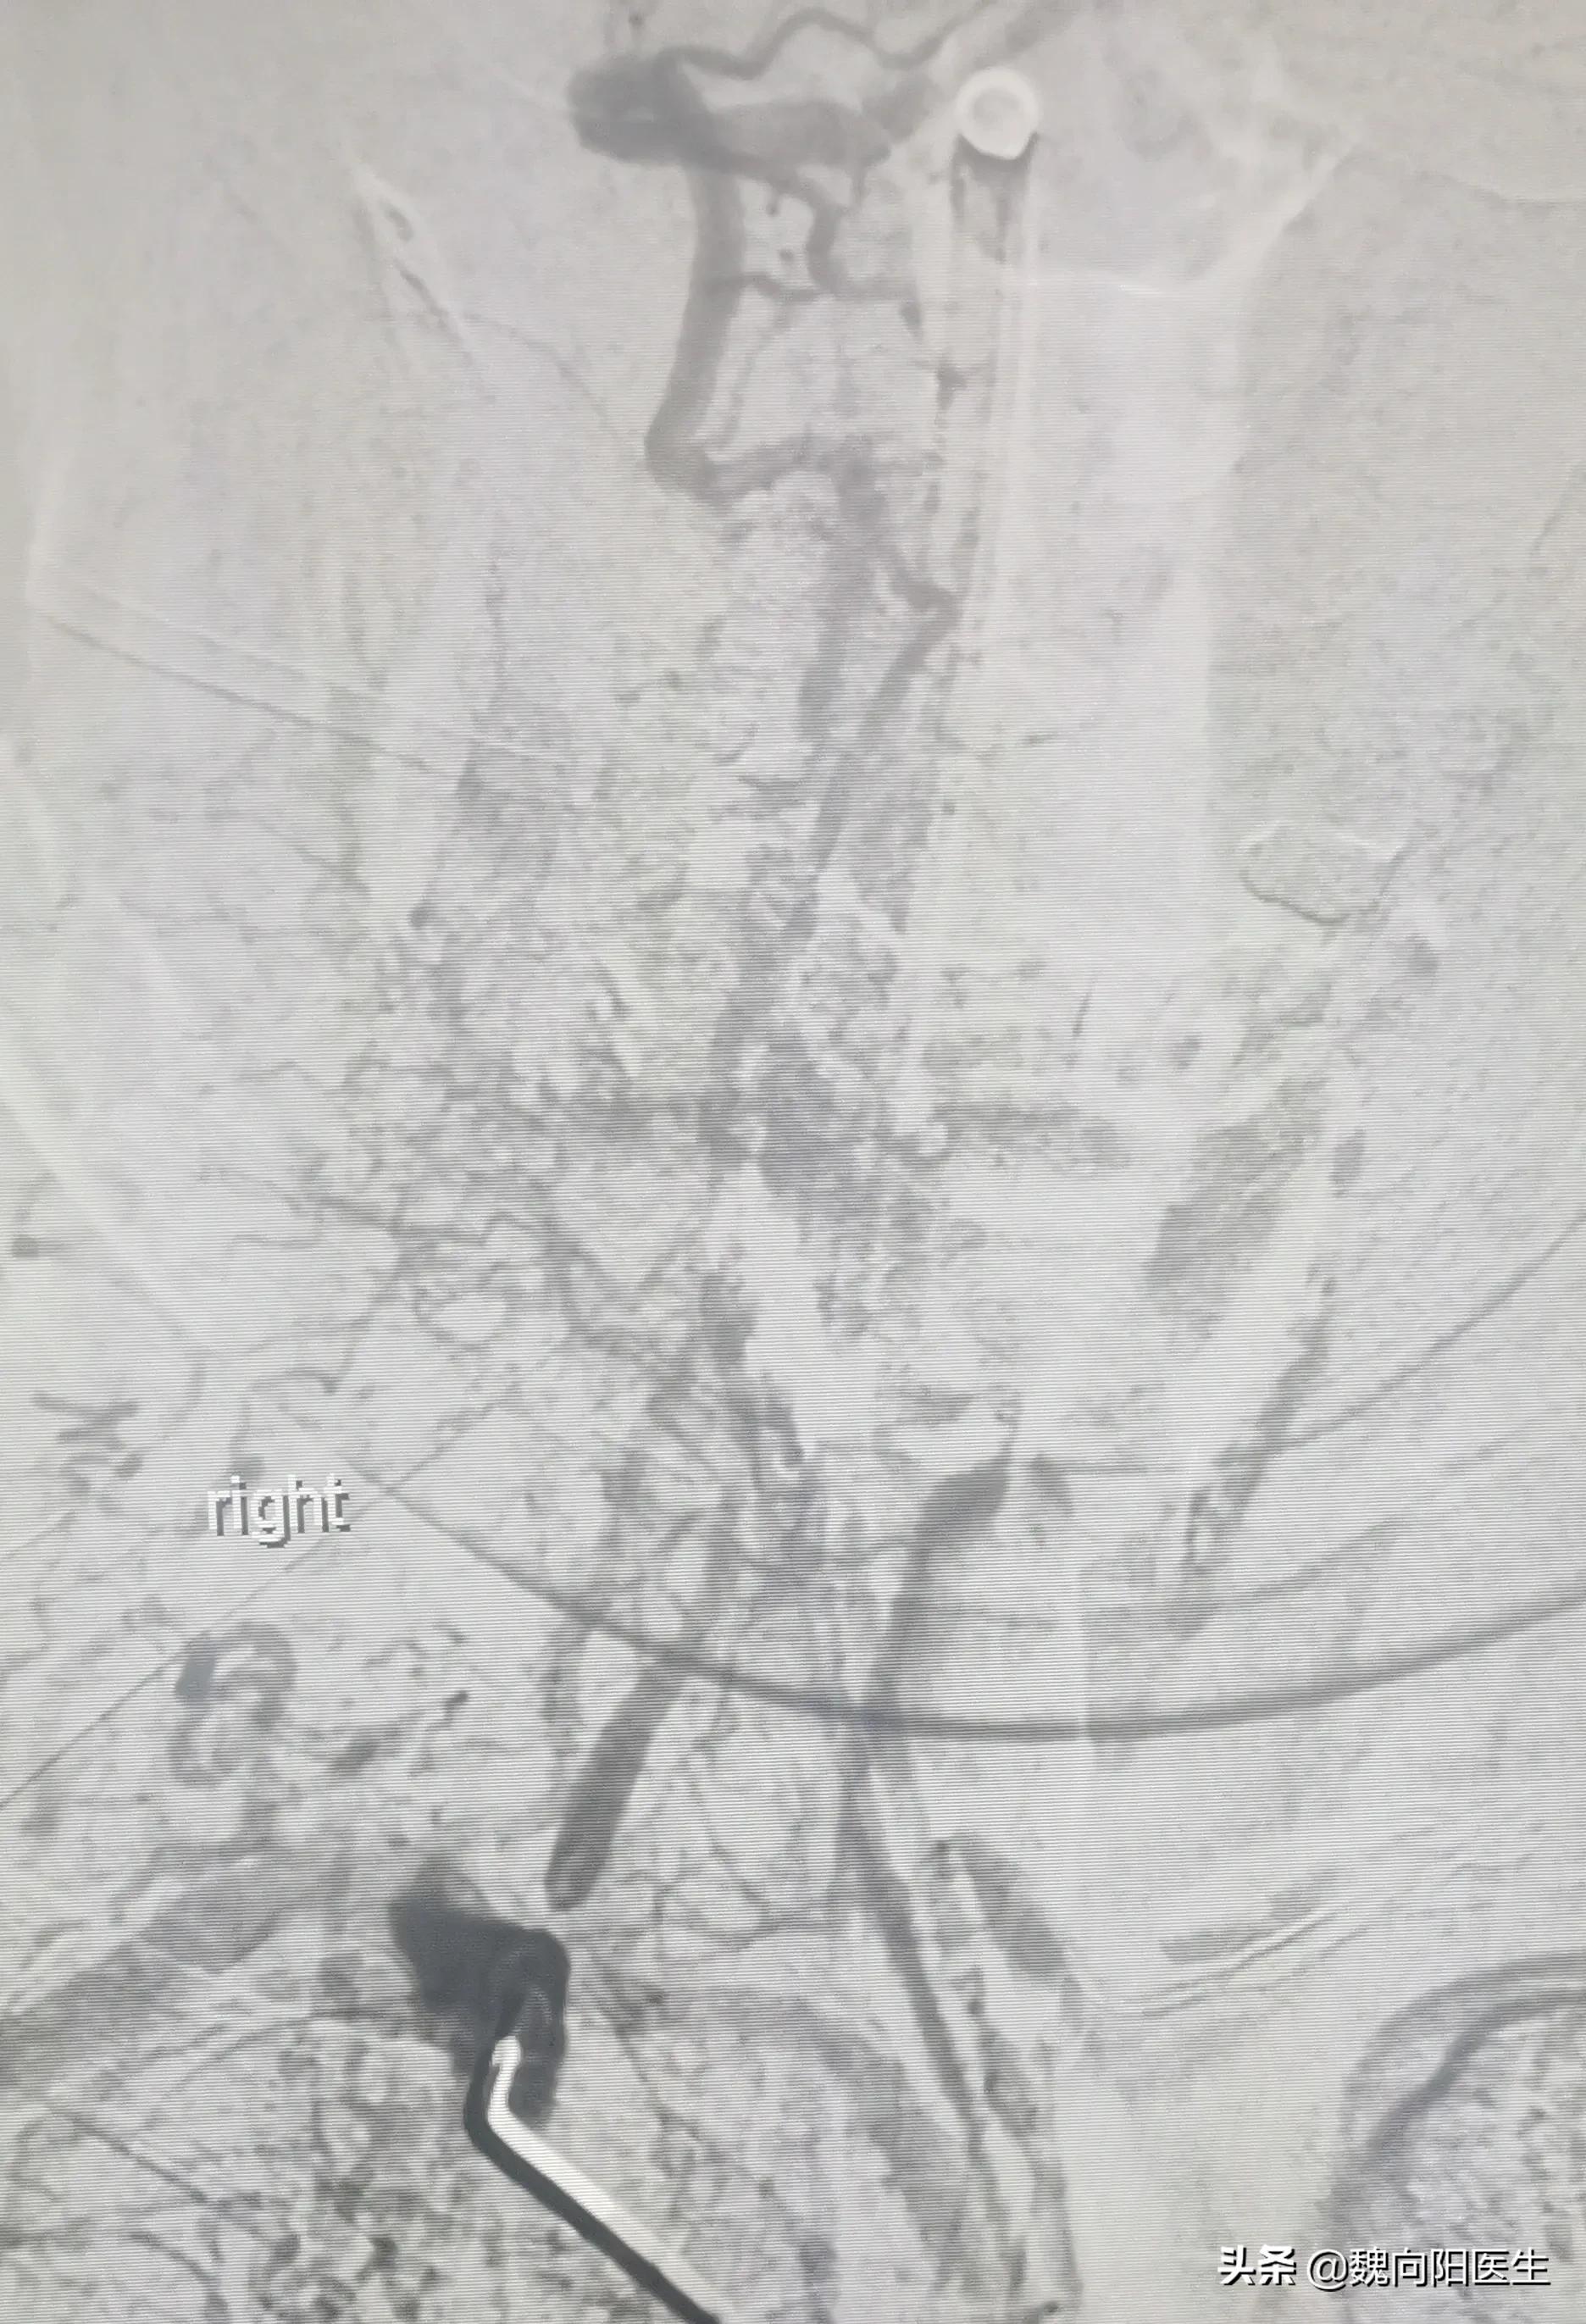

脑血管造影发现:椎动脉次全闭塞状态。

细若游丝椎动脉